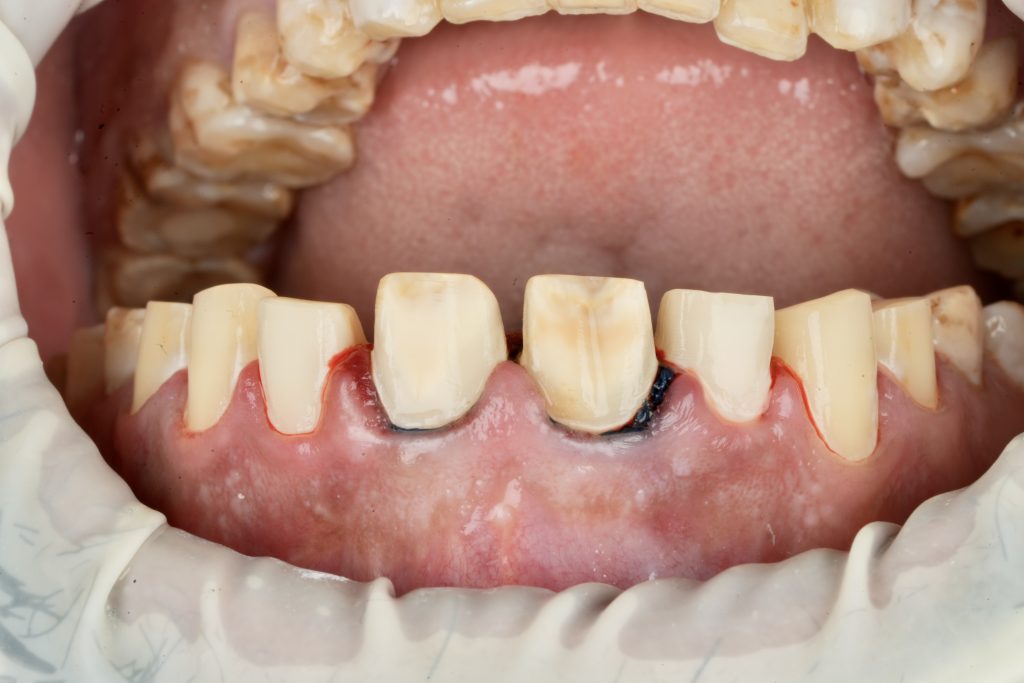

2️⃣ Guided Tooth Reduction

Using silicone indexes derived from the mock-up, controlled minimal-thickness veneer preparations (0.3–0.5 mm) were carried out under microscope magnification to ensure uniform reduction and margin clarity (Fig 2). Finish lines were placed juxta-gingivally with soft-tissue protection using Teflon and double-cord isolation.